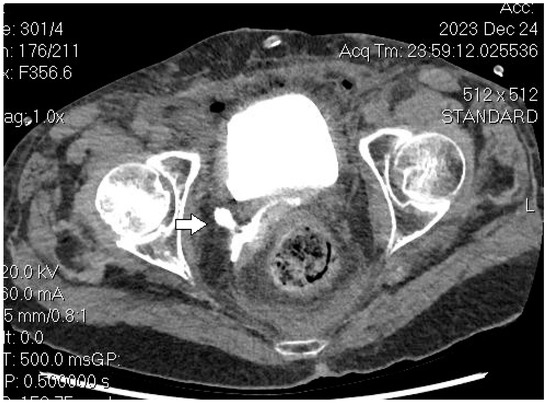

- Benoit, L.; Zerbib, J.; Koual, M.; Nguyen-Xuan, H.; Delanoy, N.; Le Frère-Belda, M.-A.; Bentivegna, E.; Bats, A.-S.; Fournier, L.; Azaïs, H. What Can We Learn from the 10 Mm Lymph Node Size Cut-off on the CT in Advanced Ovarian Cancer at the Time of Interval Debulking Surgery? Gynecol. Oncol. 2021, 162, 667–673. [Google Scholar] [CrossRef] [PubMed]

- Tardieu, A.; Ouldamer, L.; Margueritte, F.; Rossard, L.; Lacorre, A.; Bourdel, N.; Lades, G.; Sallée, C.; Monteil, J.; Gauthier, T. Assessment of Lymph Node Involvement with PET-CT in Advanced Epithelial Ovarian Cancer. A FRANCOGYN Group Study. J. Clin. Med. 2021, 10, 602. [Google Scholar] [CrossRef] [PubMed]

- Crestani, A.; Huchon, C.; Mezzadri, M.; Marchand, E.; Place, V.; Cornelis, F.; Touboul, C.; Haddad, B.; Dabi, Y.; Benifla, J.-L.; et al. A Pre-Operative Radiological Score to Predict Lymph Node Metastasis in Advanced Epithelial Ovarian Cancer. J. Gynecol. Obstet. Hum. Reprod. 2022, 51, 102464. [Google Scholar] [CrossRef] [PubMed]